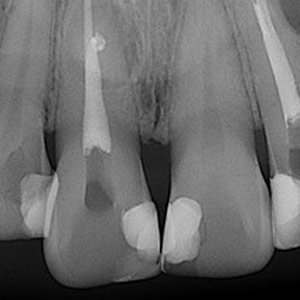

NON-SURGICAL

Oftentimes, our patients need non-surgical treatments that require minimal intervention. This intertwines with our belief that preventative maintenance and regular dental care can minimize the need for surgeries. You can rest assured that our highly trained and experienced team consistently provides the highest quality endodontic treatments and assistance available in the North Shore.